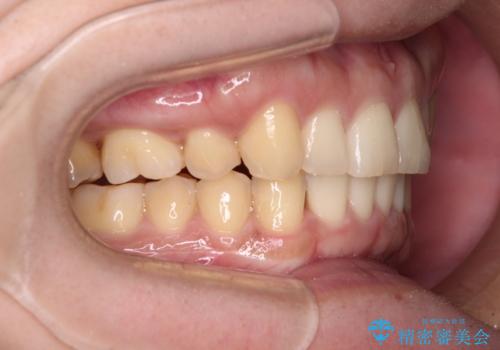

- 上顎の八重歯と前歯のデコボコを気にして来院された患者様です。

八重歯の移動量が多く、インビザライン単体での治療は困難と判断し、補助装置により八重歯移動後にインビザラインを用いることとしました。

上顎のみの抜歯矯正をインビザラインで行う場合、奥歯の前方移動がインビザラインでは苦手のため、奥歯の咬み合わせが不十分となることがあります。

今回の治療では終了時に奥歯は接触しているものの、接触の程度は物足りないものがある状態でした。今後保定期間に少しずつ奥歯の咬合を改善させていくことになります。